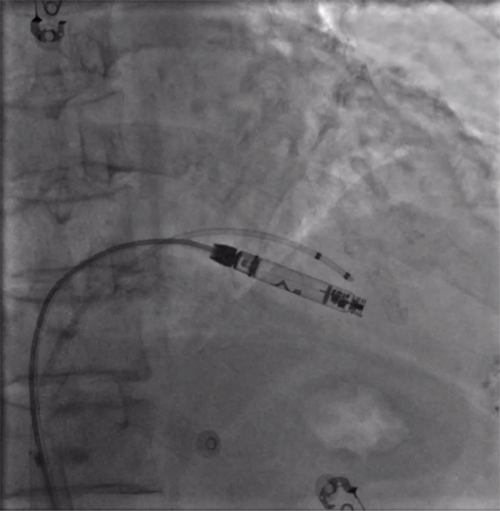

经过周密的术前准备,彭晖、孙志军两位主任带领邸北冰主治医师、柳晓娜主治医师和梁立丰医师在内的起搏电生理团队,于心脏介入手术室为患者实施手术。手术团队股静脉穿刺成功后,首先对下腔静脉进行造影并将外鞘放置送入下腔静脉,随后将新型主动固定螺旋无导线起搏器顺利跨瓣送入右心室目标位置,旋入前测试无导线起搏器各项电学参数良好,确认位置合适后旋入固定起搏器,在植入过程中动态测试起搏器各项参数以辅助判断固定程度,达到标准后进入对接栓模式,再次测试起搏器固定位置稳定、各项参数良好后释放起搏器,最后撤出鞘管,顺利完成手术。整个手术流程高效有序,医疗团队成员紧密配合,默契无间,仅耗时40分钟共同完成了这一具有挑战性的任务。

股静脉穿刺后下腔静脉造影

右室猪尾导管造影

RAO造影确认位置安全

LAO造影确认指向间隔部

电学标测参数良好,在此旋入1.5圈后进入对接栓模式,

摇摆与电学参数测试后释放起搏器

植入后右前斜

植入后左前斜